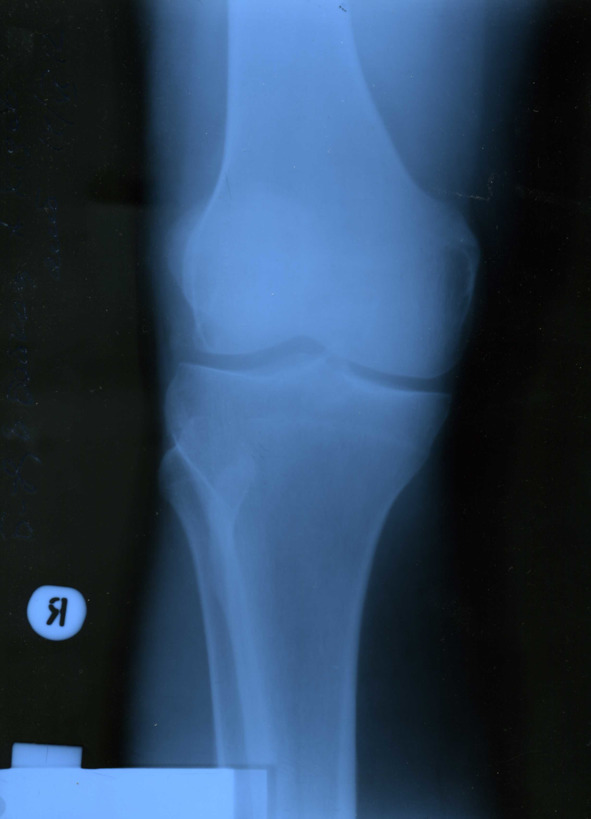

В сентябре 2012 года, когда уже оба сустава по кругу обострялись ни один раз, в очередной раз случилось обострение, и я все-таки решил обратиться к коллеге-хирургу за обследованием и профессиональной помощью. После общего осмотра было назначено рентген-обследование коленных суставов (все снимки представлены ниже).

Изменения малозаметны, но все же диагноз хронический остеоартроз подтвердил врач-рентгенолог, хирургом назначены обезболивающие средства и аппликации сустава димексидом.

Итак. Мы вместе со старшим сыном делали рентгенологическое исследование суставов и кровь на боррелиоз сдали одновременно.

Анализ ИФА ничего не выявил ни у меня, ни у сына. Кстати, на рентгене у моего старшего рентгенолог описал какую-то врожденную аномалию крестообразной связки. Но этот дефект его никогда больше не беспокоил. Здесь также можно усмотреть связь с питьевой водой, ведь фильтр для воды стоял у меня дома, и все члены моей семьи пили эту воду, может быть на так фанатично, как я.